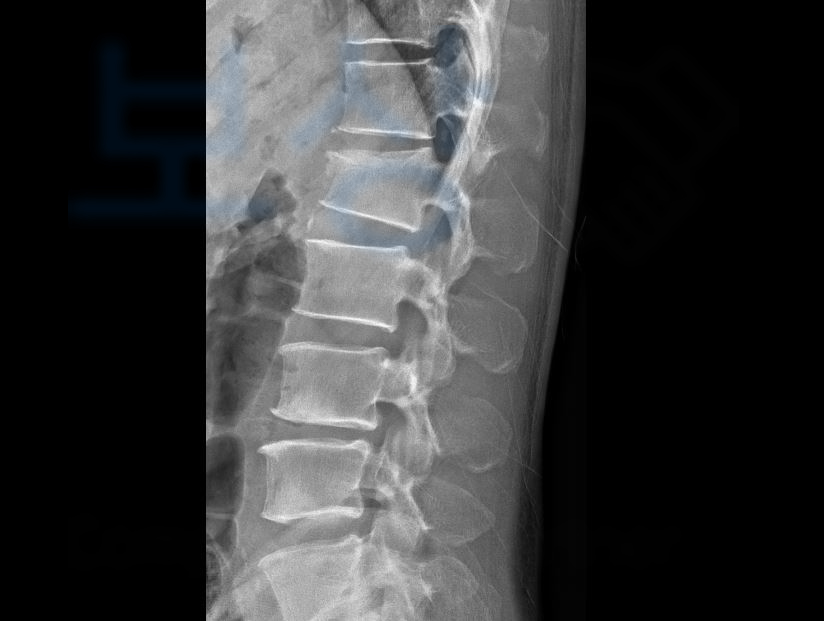

신@@님은 소방시설 공사를 위해 사다리를 이용하던 중 2미터의 높이에서 추락하는 사고를 당하셨습니다.

금번 사고로 병원에 내원하여 정밀검사를 받아보니…

요추1번압박골절과

경추부 염좌, 뇌진탕

좌측 견관절 염좌, 천골 골절

복부 좌상, 흉골 염좌 등의 진단을 받게 되었습니다.